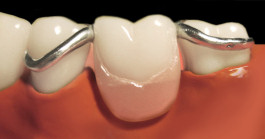

Die Klammerprothese:

Eine Klammerprothese ersetzt einen oder mehrere fehlende Zähne. Mit Hilfe von (Guss)-Metallklammern wird die Klammerprothese an den eigenen Zähnen befestigt. Die Prothese besteht aus einer metallenen und mit Kunststoff umgebenen Prothesenbasis, auf der die künstlichen Zähne sitzen. Zur richtigen Konstruktion der Prothese wird anstatt traditionellem Abdruck mit Abdruckl6ffel und Abdruckmasse ein präziser Intraoralscan (3D-Scan) vom Ober- und Unterkiefer erstellt. Die Zahnform, Zahnfarbe, Bisshöhe und Bisslage werden für jeden Patienten individuell berechnet und zusammengestellt. Ein optimaler Sitz ist sehr wichtig. Der Patient muss die Prothese herausnehmen und außerhalb des Mundes reinigen. Eine Teilprothese wird immer dann eingesetzt, wenn eine Brücke aufgrund fehlender oder instabiler Pfeilerzähne nicht mehr in Frage kommt.

Klammerprothese